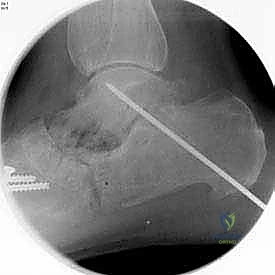

5. التثبيت الداخلي (Internal Fixation)

بعد التأكد من الوضعية المثالية للعظام، يتم تثبيتها بقوة باستخدام مسامير معدنية مجوفة من التيتانيوم (Cannulated Screws) أو شرائح معدنية خاصة. يتم إدخال المسامير تحت توجيه الأشعة السينية المباشرة (Fluoroscopy) داخل غرفة العمليات لضمان الدقة المتناهية. هذه المسامير تضغط العظام معاً وتمنع أي حركة حتى يحدث الالتئام التام.